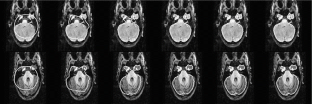

In this chapter we are concerned with variational methods in image analysis. Special attention is paid on free discontinuity approaches of Mumford Shah type and their application in segmentation, matching and motion analysis. We study combined approaches, where one simultaneously relaxes a functional with respect to multiple unknowns. Examples are the simultaneous extraction of edges in two different images for joint image segmentation and image registration or the joint estimation of motion, moving object, and object intensity map. In these approaches the identification of one of the unknowns improves the capability to extract the other as well. Hence, combined methods turn out to be very powerful approaches. Indeed, fundamental tasks in image processing are highly interdependent: Registration of image morphology significantly benefits from previous denoising and structure segmentation. On the other hand, combined information of different image modalities makes shape segmentation significantly more robust. Furthermore, robustness in motion extraction of shapes can be significantly enhanced via a coupling with the detection of edge surfaces in space time and a corresponding feature sensitive space time smoothing. Furthermore, one of the key tools throughout most of the methods to be presented is nonlinear elasticity based on hyperelastic and polyconvex energy functionals. Based on first principles from continuum mechanics this allows a flexible description of shape correspondences and in many cases enables to establish existence results and one-to-one mapping properties. Numerical experiments underline the robustness of the presented methods and show applications on medical images and biological experimental data. This chapter is based on a couple of recent articles (Bar et al., A variational framework for simultaneous motion estimation and restoration of motion-blurred video, 2007; Litke et al., An image processing approach to surface matching, 2005; Droske et al., Comput. Vis. Sci. Online First, 2008; Droske and Rumpf, SIAM Appl Math 64(2):668–687, 2004; Droske and Rumpf, IEEE Trans Pattern Anal Mach Intell 29(12):2181–2194, 2007; Rumpf and Wirth, SIAM J Imag Sci, 2008) published by the author together with Leah Bar, Benjamin Berkels, Marc Droske, Nathan Litke, Wolfgang Ring, Guillermo Sapiro, Peter Schröder, and Benedikt Wirth.

The author is grateful to Werner Bautz, radiology department at the university hospital Erlangen, Germany, for providing CT data of kidneys, as well as to Heiko Schlarb from Adidas, Herzogenaurach, Germany, for providing 3D scans of feet, and to Bruno Wirth, urology department at the Hospital zum Hl. Geist, Kempen, Germany, for providing thorax CT scans. Furthermore, the author thanks Stan Osher for pointing to the issue of elastic shape averaging and Marc Droske for discussion about the phase field approach. Finally, he acknowledges Helene Horn for her help in the careful preparation of the manuscript.